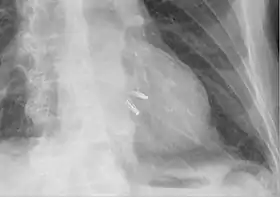

![]() Chest radiograph showing two MitraClips projecting over the heart. | |